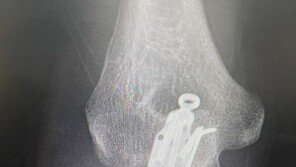

힙합그룹 다이나믹듀오 개코가 팔 골절 수술 후 근황을 밝혔다. 개코는 2일 자신의 사회관계망서비스(SNS)를 통해 “오늘 엑스레이 찍었는데 뼈가 거의 다 붙었다”라며 “그래서 내일 모레 개작실 싱글 발매”라는 글과 함께 여러 장의 사진을 게재했다. 공개된 사진에는 개코가 야외에서 …